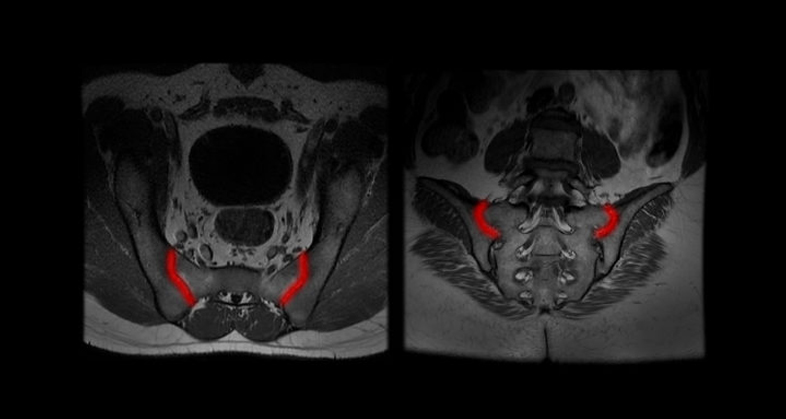

QP-Insights® emerges as a transformative breakthrough, offering a comprehensive platform for storing and managing patient data, including clinical, molecular, and imaging patient information, while integrating cutting-edge AI algorithms used as clinical decision support systems to enhance patient care and treatment outcomes. In this regard, Quibim has developed a pioneering solution for overall survival prediction in Neuroblastoma patients, leveraging the combination of clinical, molecular, and radiomics data. This solution, was externally validated, showing promising results in patients’ stratification when compared to current clinical standards.

A collaborative effort between top research and academic institutions and Quibim has yielded promising results in pediatric oncology through a European project called PRIMAGE. This project leverages predictive in-silico multiscale analytics to support personalized cancer diagnosis and prognosis, which are empowered by imaging biomarkers. This partnership equips clinicians with advanced tools to aid clinical decision-making, ultimately enhancing outcomes in Neuroblastoma patients. Quibim, in turn, strengthens its position as a pioneer by offering innovative medical imaging solutions that harness the power of integrating multi-omics data in pediatric cancer patients through advanced artificial intelligence methodologies.